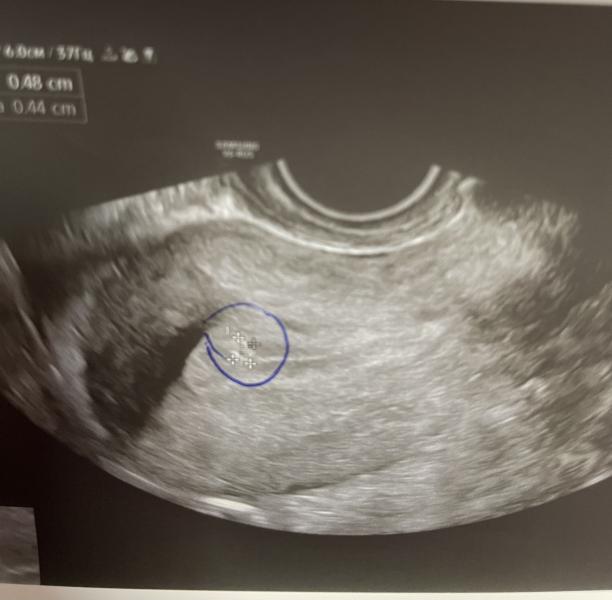

Что делать, если на УЗИ обнаружили полип?

Есть специалисты узи? Похоже это на полип?